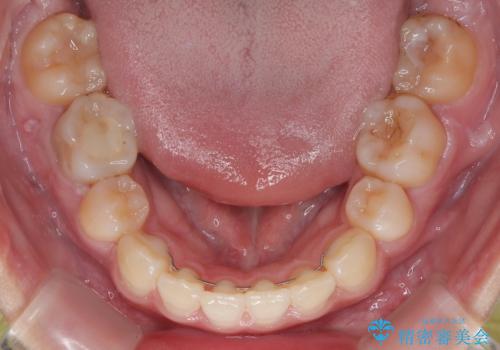

- 転勤により東京へ移られることになり転院先を探されていた患者様です。ワイヤー矯正の途中での急な転勤なうえ、今後2~3年以内に再度転勤になる可能性もあるというご事情でした。

そのため、限られた期間内に効率よく治療を完了するために、「抜歯スペースの確実な閉鎖」「深い噛み合わせ(過蓋咬合)の改善」の2点を主軸とした治療計画を立てました。